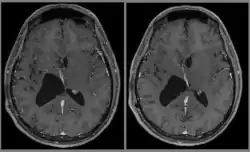

Le diagnostic est réalisé grâce à l'imagerie cérébrale, scanner ou au mieux IRM cérébrale, retrouvant cette formation hétérogène à trois composantes en général (tissulaire +/- kystique et calcique), avec rehaussement partiel à l'injection de produit de contraste.

Elle permet d'étudier les rapports avec les zones fonctionnelles du cerveau (notamment le pilier du fornix, un des composants du circuit de Papez responsable de la mémoire antérograde), le système vasculaire (réseau veineux profond), ainsi que le retentissement de la tumeur sur le cerveau (effet de masse de par l'hydrocéphalie, œdème, hémorragie, engagement…).

Dans tous les cas, un examen d'IRM (bi-)annuel sera prescrit à vie, afin de surveiller le résidu tumoral (rares sont les cas où la chirurgie a permis d'enlever la totalité de la tumeur). Les céphalées peuvent perdurer pendant des années, dues au traumatisme cicatriciel post-opératoire.